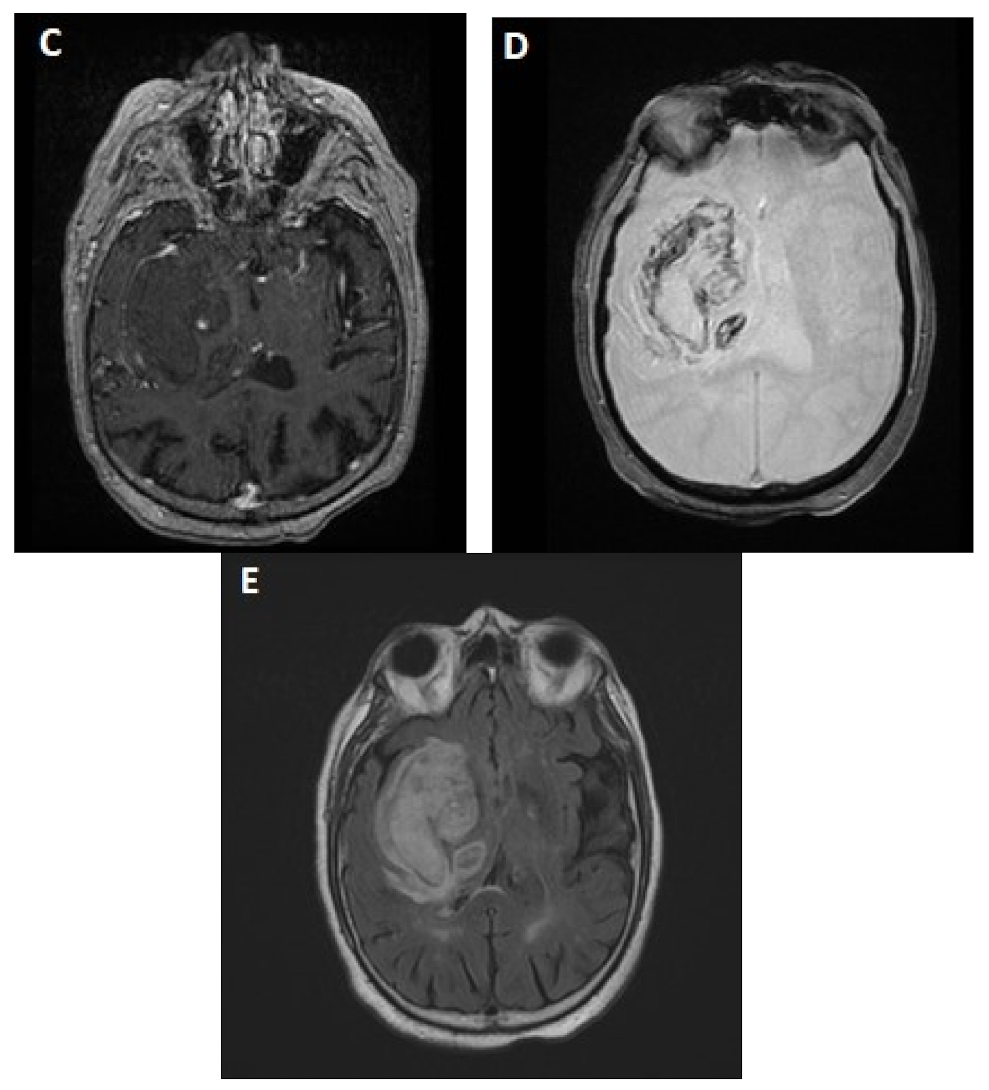

3. Imaging to Predict Ich Expansion

3.2. Value of CT-Perfusion

4.2. CT-Perfusion